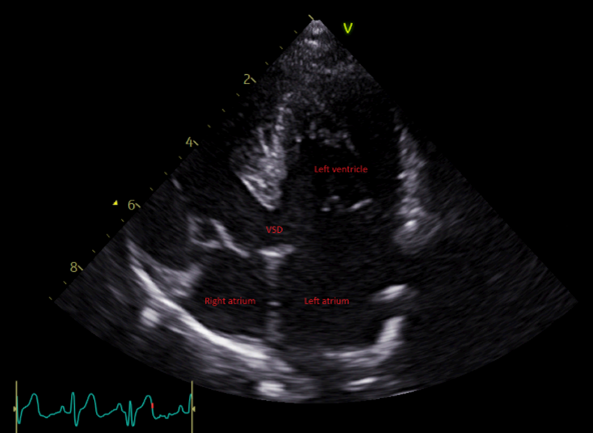

Ventricular septal defects (VSD) (Figure 5) result from the incomplete closure of the interventricular septum, the wall that divides the right and left ventricles.

On echocardiography, a large defect can be visualised as an anechoic region of the interventricular septum, whereas small defects can be challenging to appreciate using a two-dimensional view. Perimembranous defects are best seen on a right parasternal four- and five-chamber view. A right parasternal short-axis view at the base of the heart often shows turbulent flow on the margin of the aortic structures.

Colour Doppler is often required to detect small defects (Figure 6). This technique highlights the turbulent flow across the defect. Spectral Doppler helps our understanding of flow velocities and the presence of PHT.

Secondary changes include left atrial and ventricular enlargement, aortic insufficiency or signs of PHT in cases of right-to-left shunts (with pulmonary artery dilation and right ventricular hypertrophy).